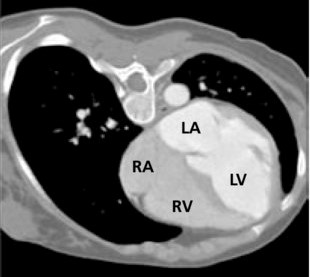

However, some researchers [15, 32] have shown that well-trained models do not perform well when the testing images come from a different statistical distribution from the training images. This domain shift problem is common in real-world medical diagnosis since medical images at various steps of the clinical procedure are often obtained with different physical properties [6]. For instance, Magnetic Resonance Imaging (MRI) and Computed Tomography (CT) play complementary roles in cardiac disease diagnosis while also exhibiting different appearances (See Fig. 1). That difference post challenges for analyzing the MRI and CT images in clinical diagnosis.

MM-WHS Dataset contains 20 labeled CT 3D images and 20 labeled MRI 3D images, which are unpaired. The original size of all images is 240220, which are cropped with a Region of Interest (ROI) of 192 × 192.

Similar to [33, 34], we include the following three structures in MS-CMRSeg dataset for segmentation: the myocardial (MYO), the left ventriculus (LV), and the right ventriculus (RV). In MM-WHS Dataset, we include five structures: the myocardial (MYO), the left ventriculus (LV), the right ventriculus (RV), the left atrium blood cavity (LA), and the right atrium blood cavity (RA). For both datasets, We remove the LGE-MRI ground truth during bSSFP to LGE-MRI experiments, remove the bSSFP ground truth during LGE-MRI to bSSFP, and remove the MRI ground truth during CT to MRI experiments. The train-test split strategy is consistent with [5, 2, 33, 34]